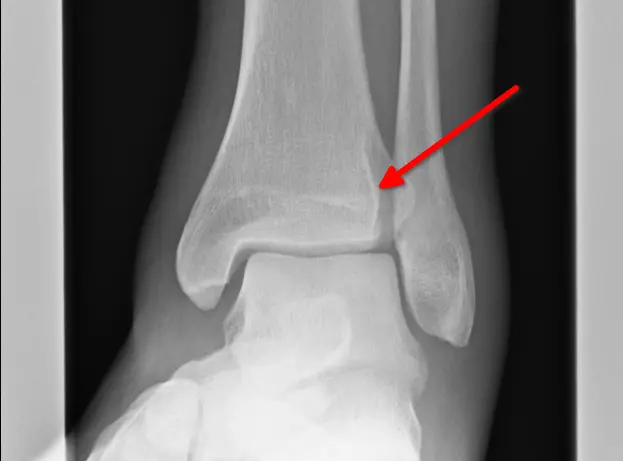

Zum Glück legte meine Freundin bei ihrem Hausarzt ein gutes Wort für mich ein. Also ging es am Montag zunächst in die Praxis, dann zur Radiologie: erst Röntgen, zurück zur Praxis, anschließend noch einmal zum CT. Die ersten Befunde ließen nichts Gutes erahnen, von einem leichten Bruch war die Rede.

Der Arzt organisierte schließlich einen Termin in der Unfallchirurgie im Krankenhaus. Eine Stunde später saß ich dort, erneut beim Röntgen. Und siehe da: Auch das Wadenbein hatte einen Knacks.